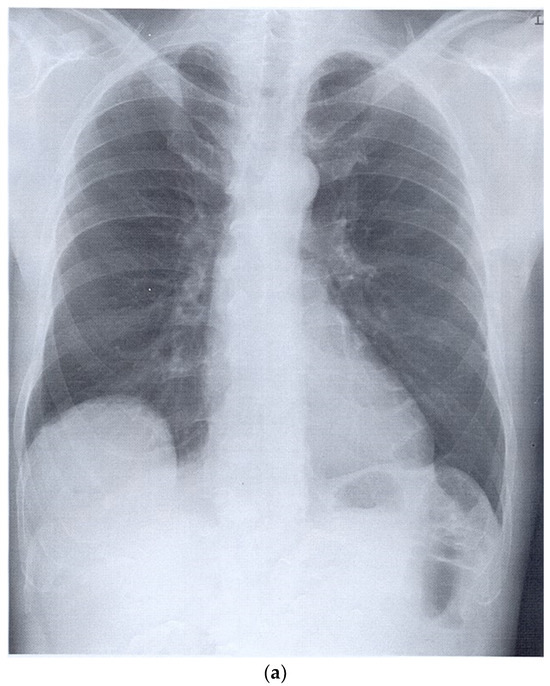

- Zhou, S.; Zhao, J.; Song, X.; Zheng, M.; Li, H.; Pan, Y. Imaging manifestations of B-mode ultrasound combined with CT in tuberculous pleuritis patients and the diagnostic value. Exp. Ther. Med. 2018, 16, 2343–2348. [Google Scholar] [CrossRef] [PubMed]

- Rea, G.; Sperandeo, M.; Lieto, R.; Bocchino, M.; Quarato, C.M.I.; Feragalli, B.; Valente, T.; Scioscia, G.; Giuffreda, E.; Barbaro, M.P.F.; et al. Chest Imaging in the Diagnosis and Management of Pulmonary Tuberculosis: The Complementary Role of Thoraci Ultrasound. Front. Med. 2021, 8, 753821. [Google Scholar] [CrossRef] [PubMed]